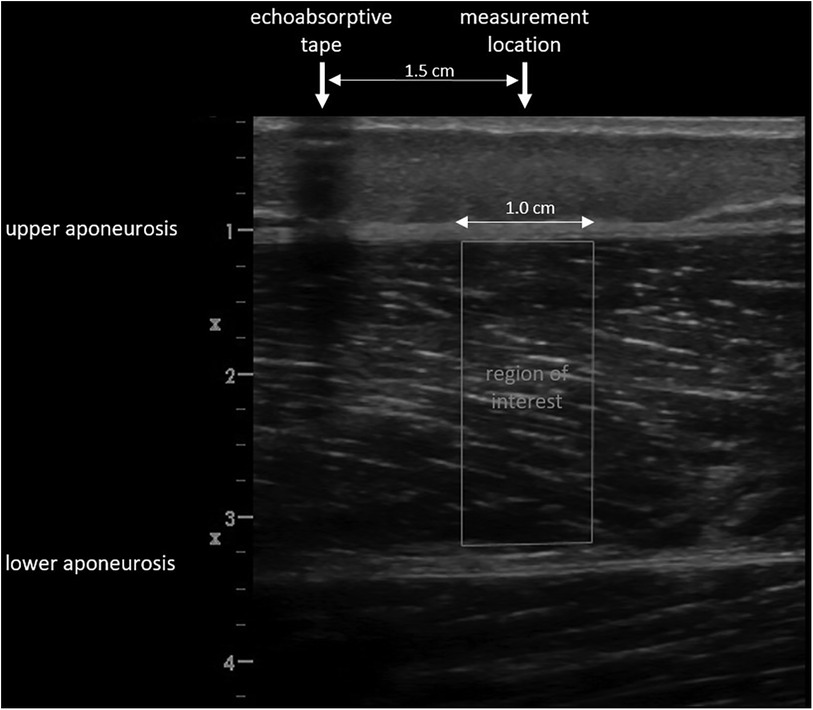

describe the spread; here () are the variances of the Gaussian in the u- and v- directions respectively, and θ is the rotation of the Gaussian ellipsoid. The spectral data was fit to the ellipsoidal Gaussian using an unconstrained multivariable simplex method (22). Spatial frequency parameters, including four new parameters (Table 2), were extracted from the model after fitting was achieved. The kernel dimensions (number of pixels) was set the same as Bashford et al. (11) as the structures under analysis were at similar image depths and similar ROI sizes. A standardized ROI was selected by measuring a 1 cm wide rectangular area of the GM and VL from the upper to the lower aponeuroses at the muscle belly, at a predefined position located such that the center of the ROI was 1.5 cm from the echoabsorptive tape; i.e., the vertical edges of the ROI were 1 cm and 2 cm distal from the echoabsorptive tape (Figure 6). The SFA analysis yielded six spatial frequency parameters: peak spatial frequency radius [PSFR], peak −6 dB width [P6], PSFR/P6 [Q6], normalized peak value of amplitude spectrum [Amax], power within peak [PWP], and peak power percent [PPP] (Table 2).